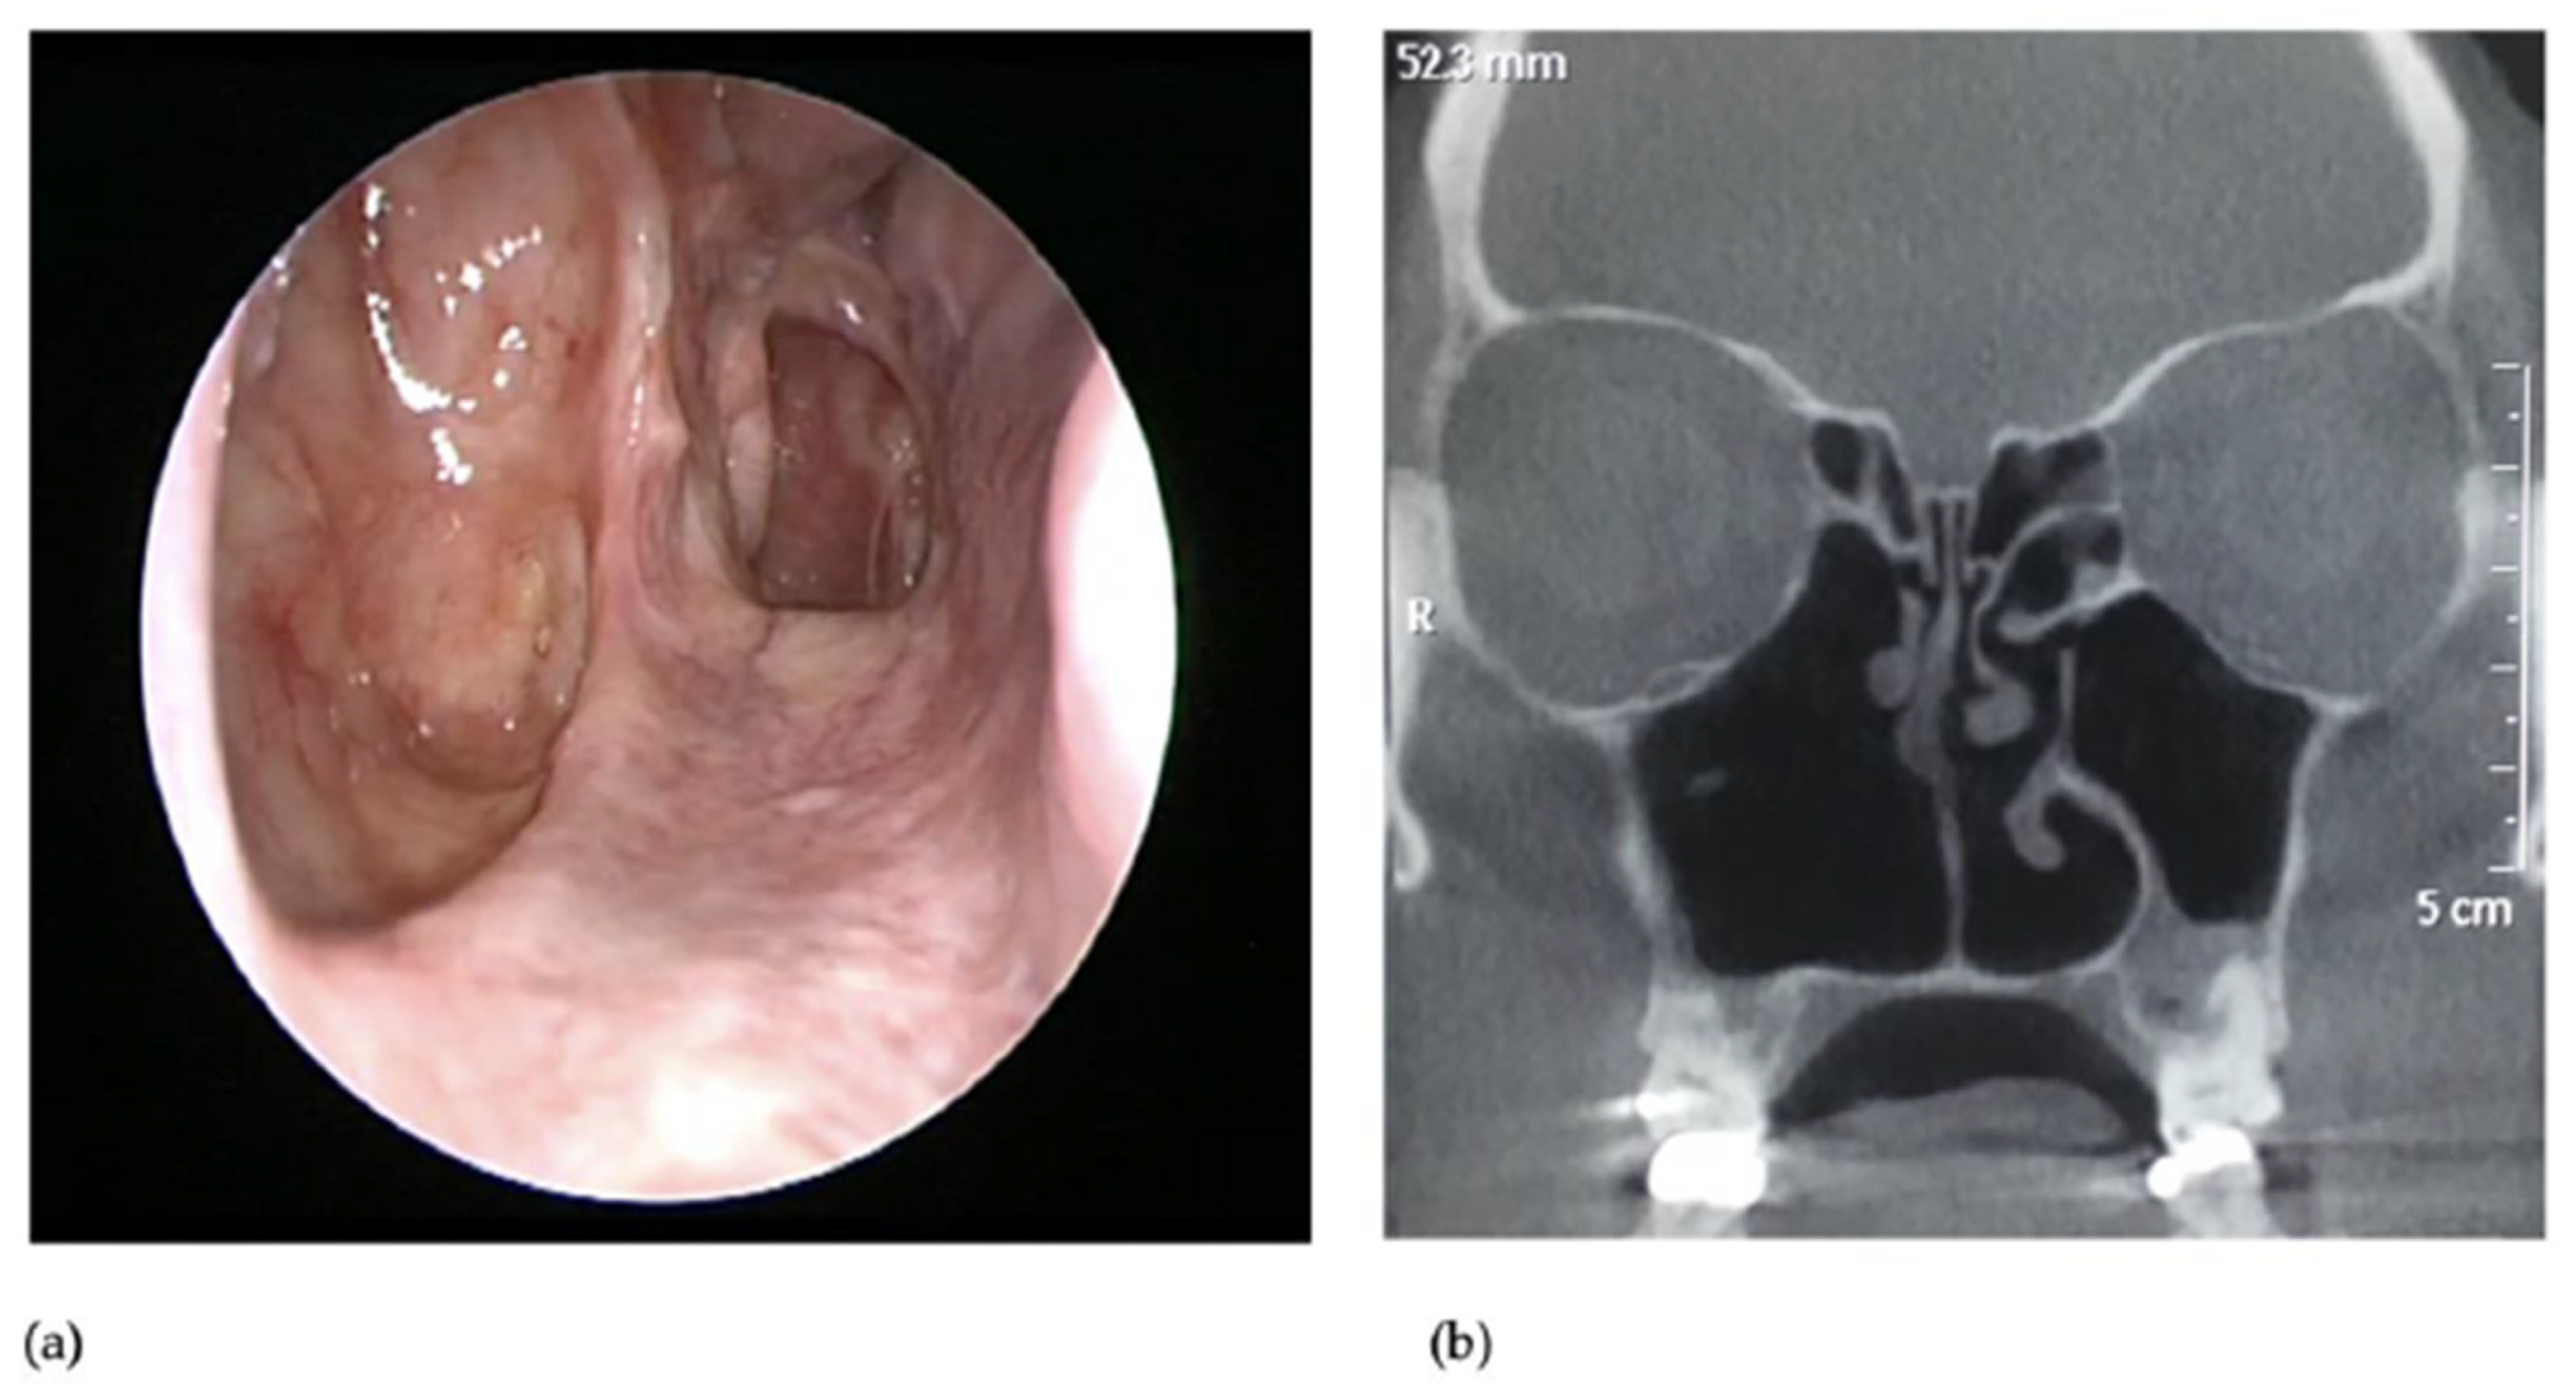

3. Presentation